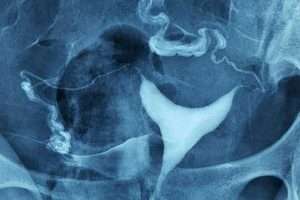

Myom

Rahim sağındaki iri myom kitlesi rahim boşluğu alt kısmının uzamasına ve sola doğru itilmesine sebep olmuş.